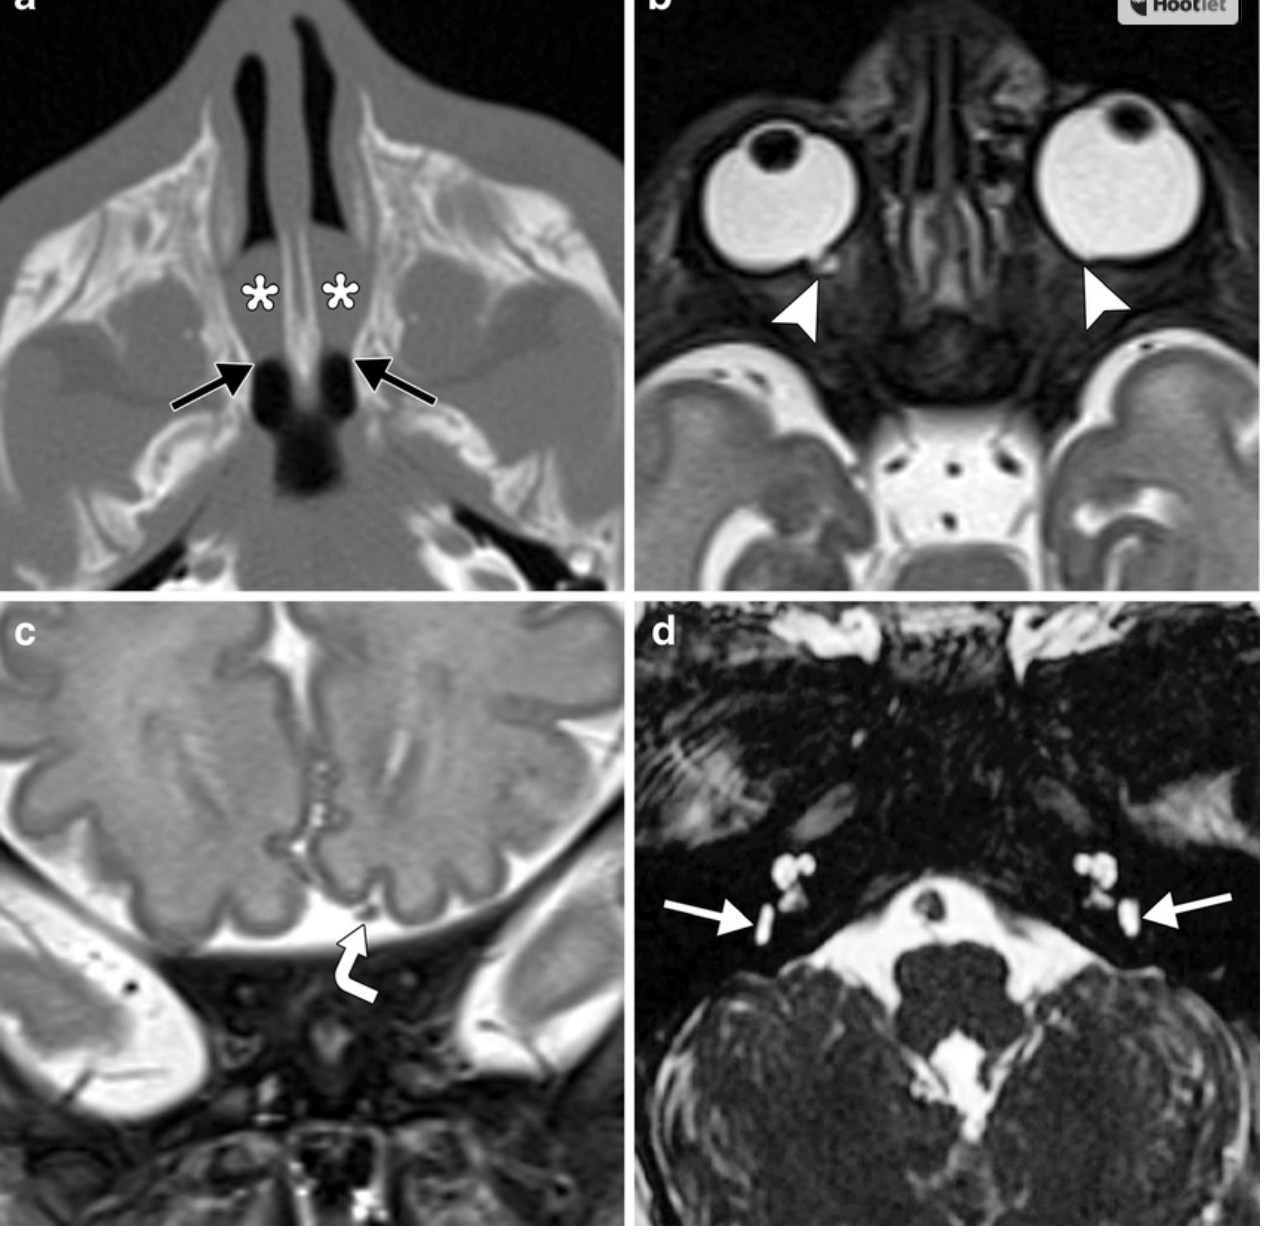

CHARGE syndrome. Axial CT image in a 6-day-old boy (a) shows bilateral bony and membranous choanal atresia with a thickened vomer and medial deviation of the lateral nasal walls at the level of the choanae (black arrows). There are secretions layering within the nasal cavities (*). Axial T2-weighted MRI at 4 days of age (same patient) (b) shows bilateral colobomas (arrowheads). Coronal T2weighted MRI (c) shows that the olfactory apparatus is absent on the right, but intact on the left (curved arrow). Axial CISS (constructive interference in steady state) image (c) shows bilateral absent semicircular canals and hypoplastic vestibules (white arrows). There is also bilateral cochlear nerve aperture and internal auditory canal stenosis

https://www.researchgate.net/figure/CHARGE-syndrome-Axial-CT-image-in-a-6-day-old-boy-a-shows-bilateral-bony-and_fig8_270650182